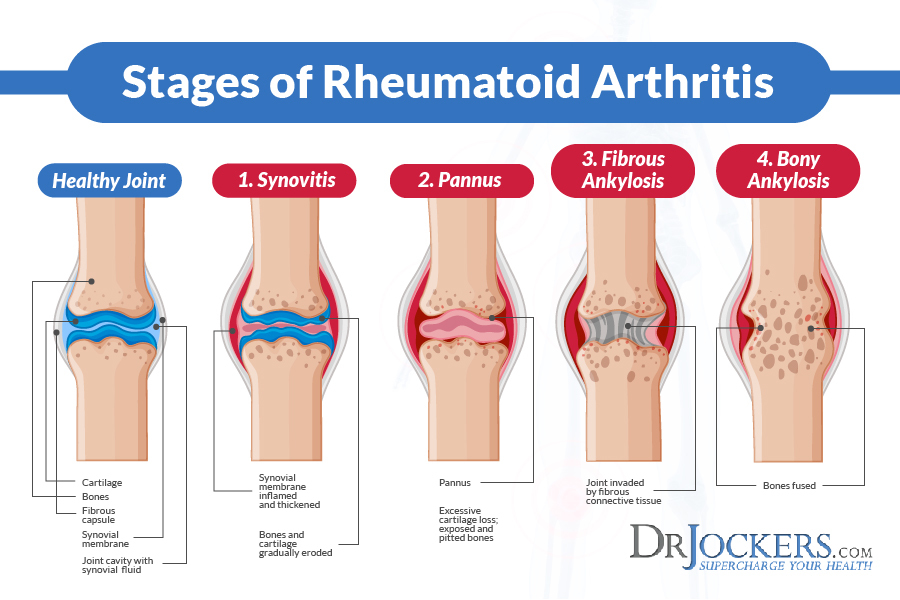

ب.آرتریت روماتوئید:این آسیب به عنوان یکی از بیماری های خود ایمنی بدن طبقه بندی می شود این عارضه یک حالت التهابی مزمن است که بیش از سایر بافت های بدن مفصل – وتر وغلاف وتر (فاسیا)را عضلات و کیسه زلالی را درگیر می کند .این بیماری در زنان سه برار مردان است معمولا در محدوده سنی 20تا 30یا 45 تا 55 سال آغاز می شود علامت اول این بیماری تورم پرده سینوویال است که پرده یسینوویال شروع به ساخت بافتی به نام پانوس می کندپانوس غضروف مفصلی را فاسد می کند

تغییرات پاتولوژیک آرتریت روماتوئید:اولین مرحله التهاب غشای سینوویال(سینوویت)است که بارسوب پروتئین (فیبرین)تشدید می شود.در نتیجه التهاب مایع به درون مفصل ترشح وموجب تورم می شود و بافت ملتهب به سمت مرکز فضای مفصلی پیشروی می کند وسطوح مفصلی .رباط ها ووتر های اطراف را می پوشاند درهمین زمان غضروف مفصلی به صورت منظم از سطح خود به طرف استخوان زیرین تخریب و در استخوان مجاور آن کیست تشکیل می شود همچنان که بافت ملتهب جای خود را به بافت زخم می دهد کپسول مفصلی ضخیم و در نتیجه مانع تحرک مفصل می شود درد و تورم .خشکی مفصل خصوصا صبح زمان بیداری .تغییر شکل مفصل .برای این بیماری درمان وجود ندارد ولی می شود ان را کنترل کرد در (عکس الف و ب مشاهده شود مفصل زانو و انگشتان دست )

عکس (الف)